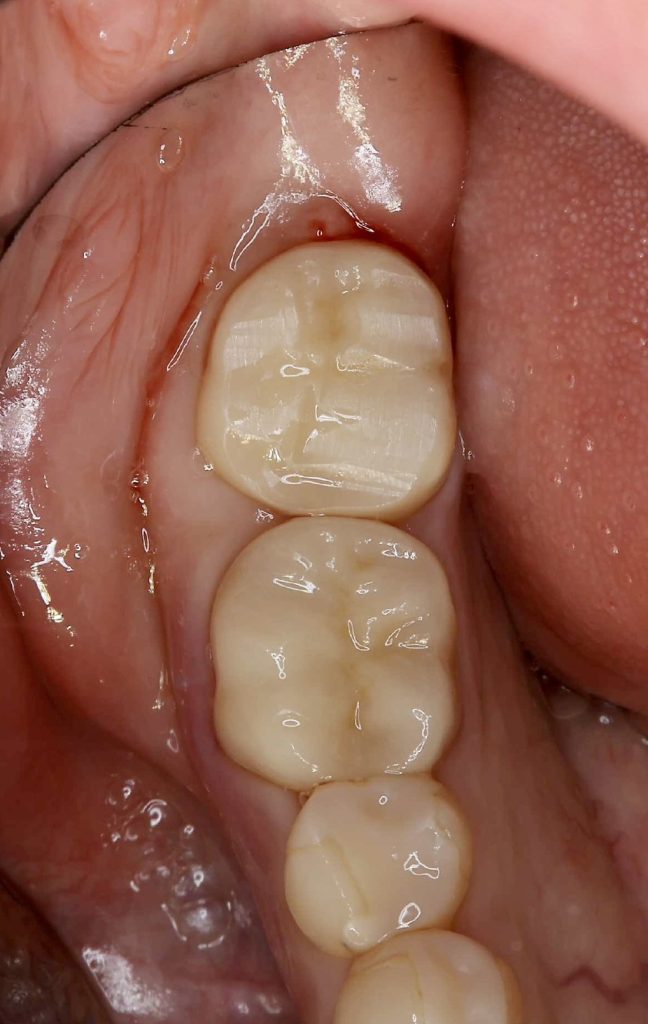

30代、女性、右下に違和感があることを健診中に申され、インプラント治療を行いました。

| 治療内容 | 抜歯即時インプラント |

| 治療期間 | 8週間 |